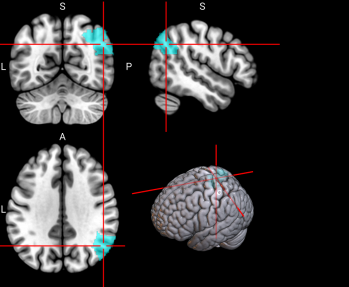

65,

66

L & R Inferior parietal gyrus, excluding supramarginal and angular gyri (IPG)

The inferior parietal gyrus is involved in attentional, semantic, and social cognitive functioning [65].

/word/media/image14.png/word/media/image14.png